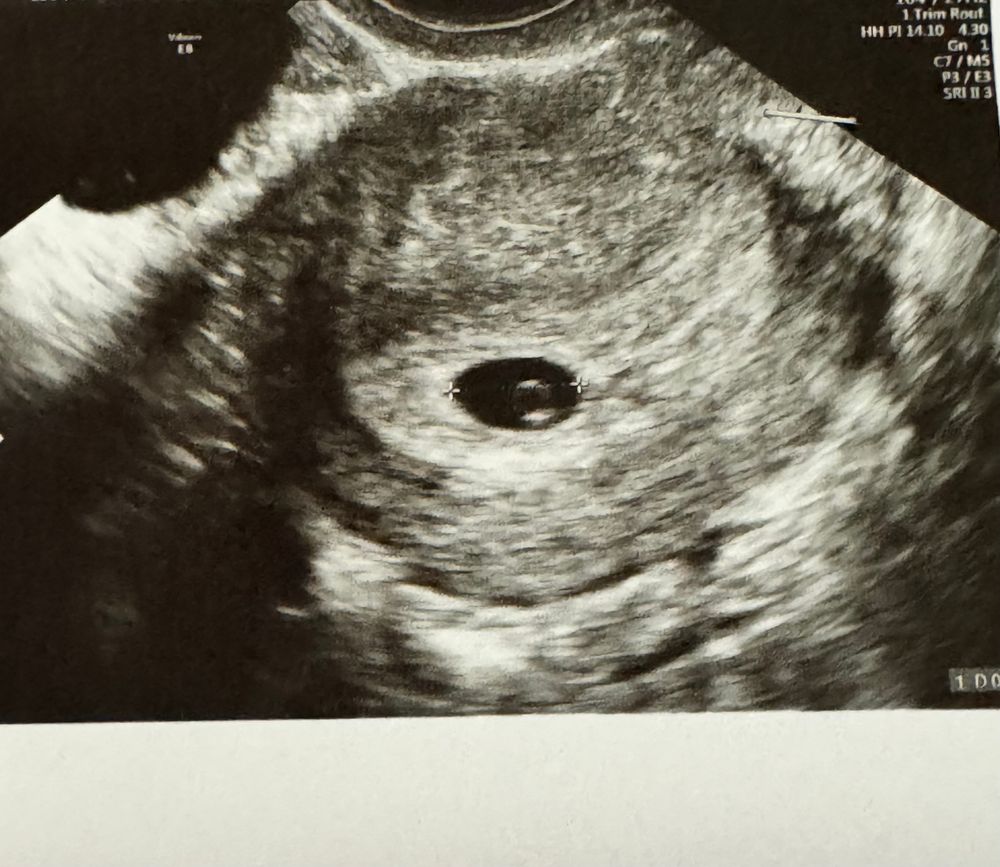

Только приехала с УЗИ.. Слышала сердечко, по месячным 5,5, а по акушерским 6-7 недель.. Изображение